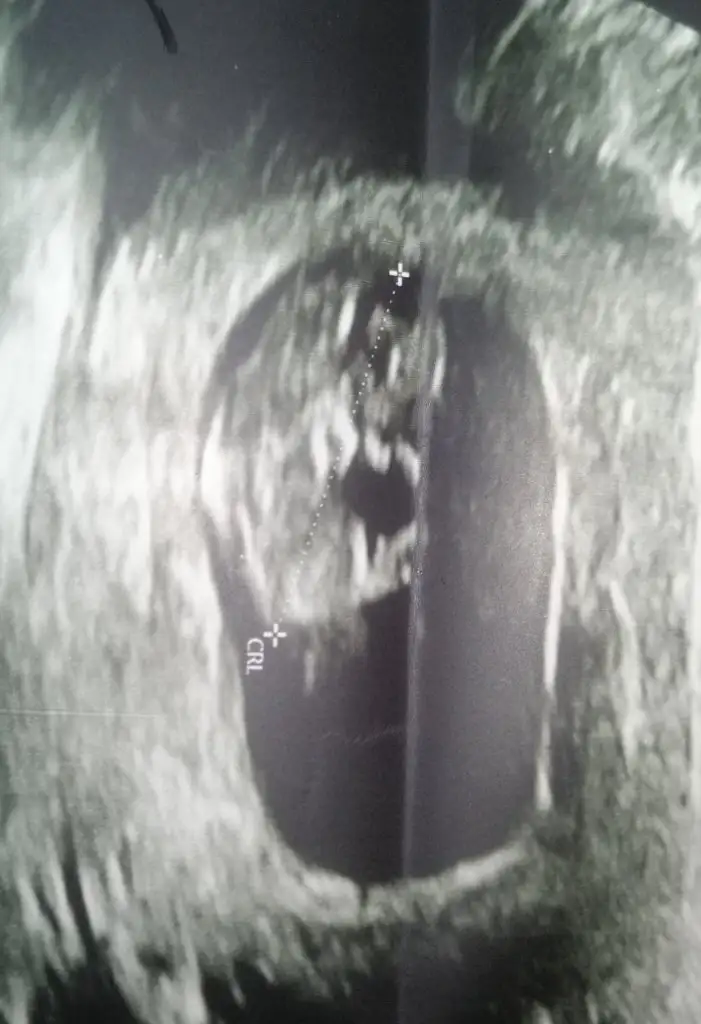

Yapısı erkek gibiBizimkinede bakar mısınız bir doktor kız dedi biri erkek burdada bir ara paylaşmıştım ama şimdide önünde kordon var yine öğrenemedim rica etsem anlayanlar bakabilir mi üç kızım var inşallah saglikli bir erkek istiyorum hayirlisiyla

Benimkinide yorumlar mısınYapısı erkek gibi

Çok erken en iyi 11 12 13 haftalar olmalı şimdilik kız yönünde ama yanıltabilir

Emin olamadımBenimkinide yorumlar mısın Eki Görüntüle 2896165

Kız görünüyor

bu yorum bana mı acaba :)Emin olamadım şimdilik erkek yönünde ama en iyi 11 12 13 haftalar olmalı